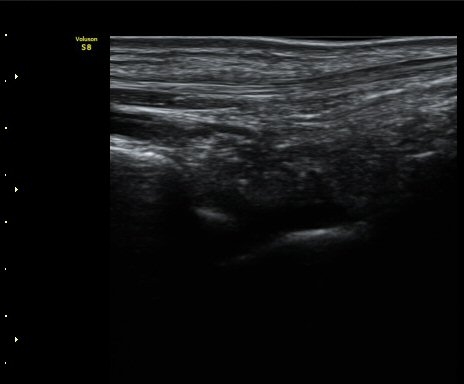

¹ß¸ñ°üÀý Á¾´Ü¸é°Ë»ç¿¡¼­ °üÀý³» ¼ö¾×Àú·ù°¡ °üÂûµÈ´Ù(±×¸² 1).

±×¸²1) ¹ß¸ñ°üÀý Á¾´Ü¸é°Ë»ç±Û